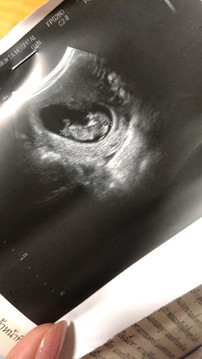

บ้านนี้ตอน 11 วีคค่ะ

น้องเต่าคะ 🤣❤️😊☺️

9วีคคะ เจอเจ้าก้อน